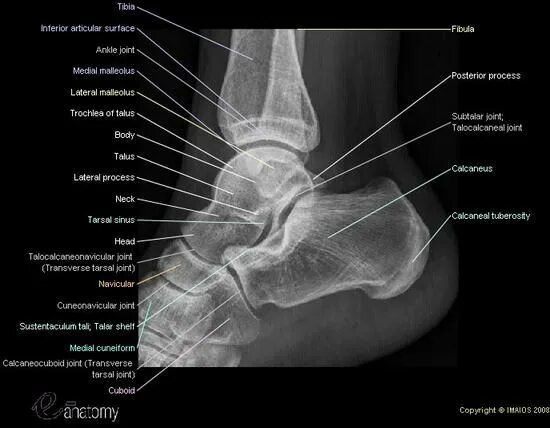

Латеральная лодыжка латынь